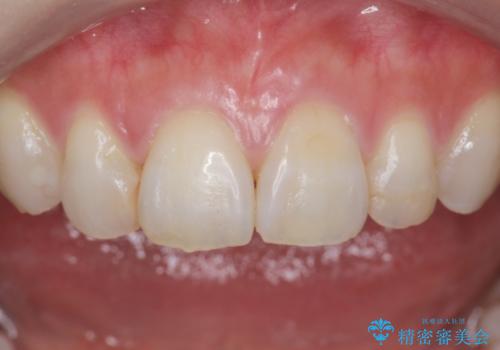

- う蝕治療や矯正治療を終えた患者様です。

歯ぎしりや歯の保護のためにナイトガードを作製しました。